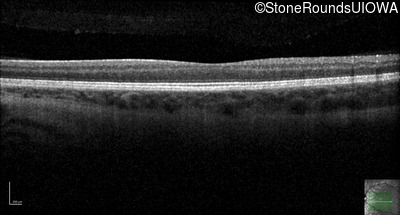

Optical Coherence Tomography - Left - 20/200

Exemplar / OCT Stack

OCT Stack